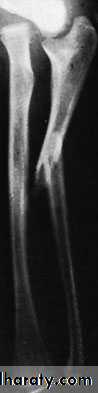

X-RAY

Both bones are broken, either transversely and at the same level or obliquely with the radial fracture usually at a higher level. In children, the fracture is often incomplete (greenstick) and only angulated.